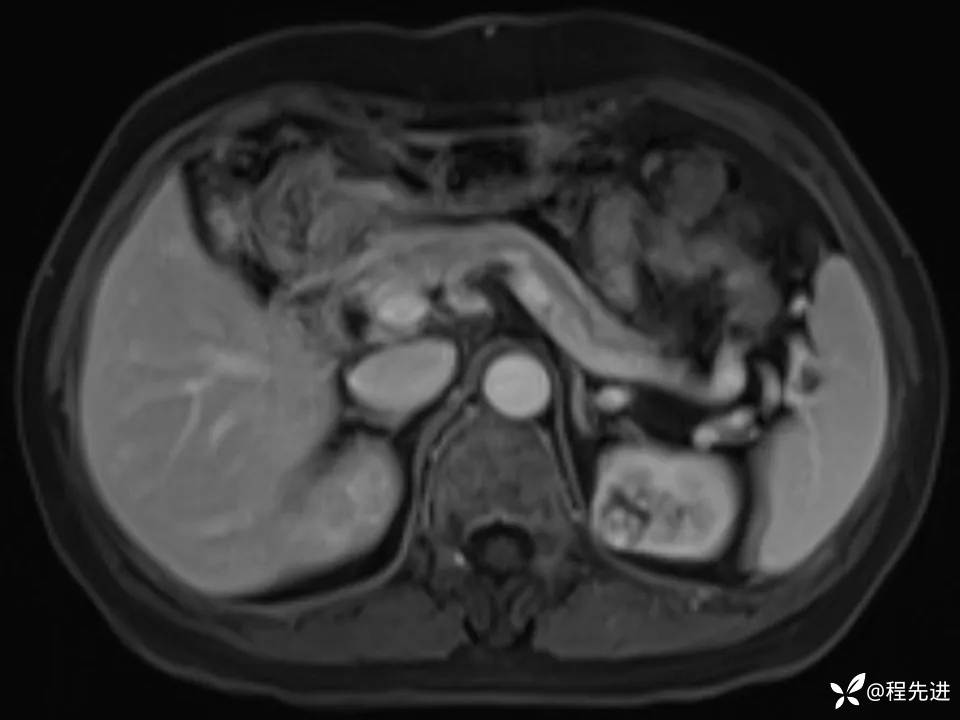

患者性别:女

患者年龄:67岁

简要病史:体检发现左肾占位,无临床症状,实验室检查无殊。

CT、MRI平扫+增强: